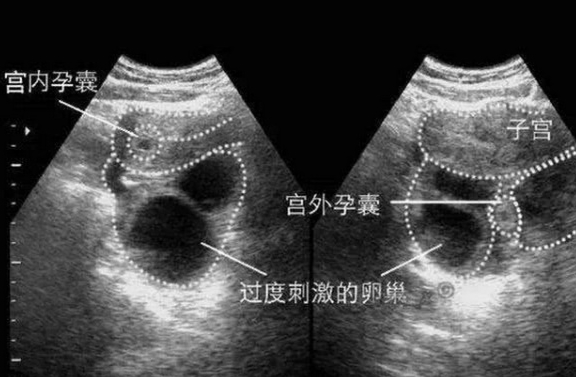

3、超聲檢查:確定妊娠部位及胚胎是否存活;

宮外孕,即受精卵在子宮以外的部位著床,最常見的是輸卵管妊娠,宮外孕如不及時發(fā)現(xiàn)并處理,可能導(dǎo)致嚴重出血、休克甚至危及生命,了解宮外孕的相關(guān)知識,尤其是其早期癥狀和處理時機,對于女性健康至關(guān)重要。